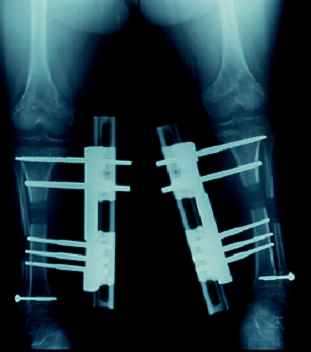

術後所見